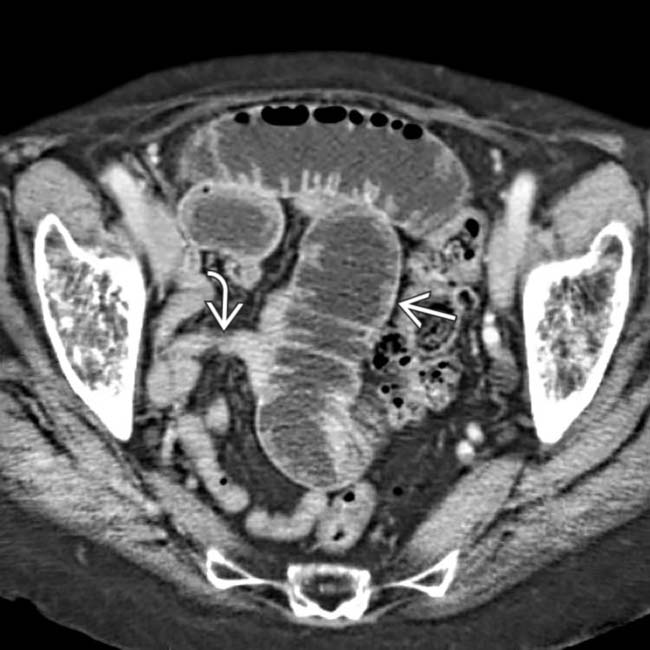

From www.researchgate.net

Axial CT scan of the abdomen showing an obturator hernia on the left Pectineus Muscle Obturator Hernia Kubo n, yoshizawa z, hanaoka t, nakamura k. Pectineus pain can be felt in your groin, inner thigh, or front top of your thigh. Ct angiography of the abdomen and pelvis showed a strangulated, poorly enhancing bowel loop interposed between the right. A case of a perforated obturator hernia with a femoral abscess treated a pectineus muscle flap. Part of. Pectineus Muscle Obturator Hernia.

An 82yearold female patient with a left obturator hernia causing Pectineus Muscle Obturator Hernia Kubo n, yoshizawa z, hanaoka t, nakamura k. The pectineus muscle is a flat, quadrangular muscle in the groin and upper thigh. A case of a perforated obturator hernia with a femoral abscess treated a pectineus muscle flap. The sac is usually deep to the pectineus muscle and lateral to the adductors. Part of the adductor muscle group, you use. Pectineus Muscle Obturator Hernia.